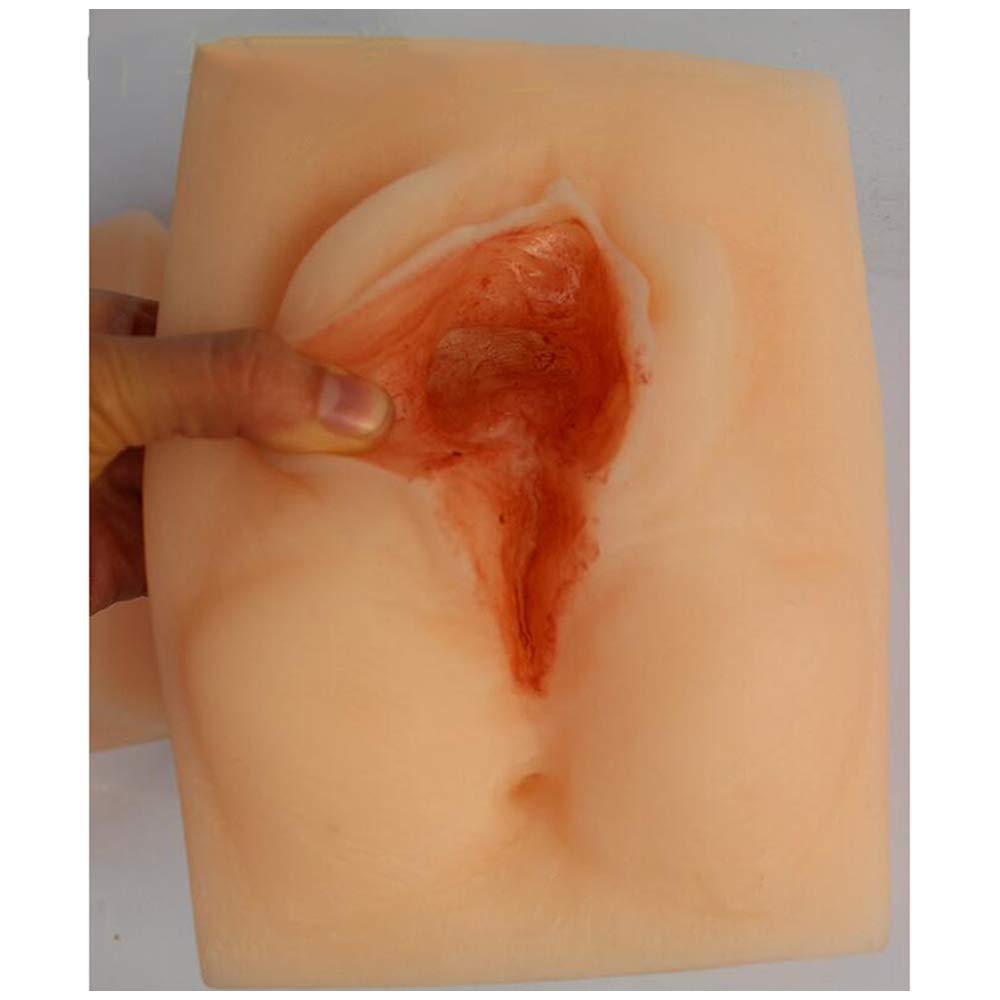

🩺 Elevate your suturing skills with lifelike precision and zero downtime!

The oBlosdhVulva Suture Practice Model is a high-fidelity female perineal incision training tool featuring three distinct incision sites. Made from environmentally friendly PVC, it offers realistic skin texture and durability for repeated use. Ideal for medical students and professionals, it requires no assembly and supports efficient, hands-on learning in gynecological suturing techniques.